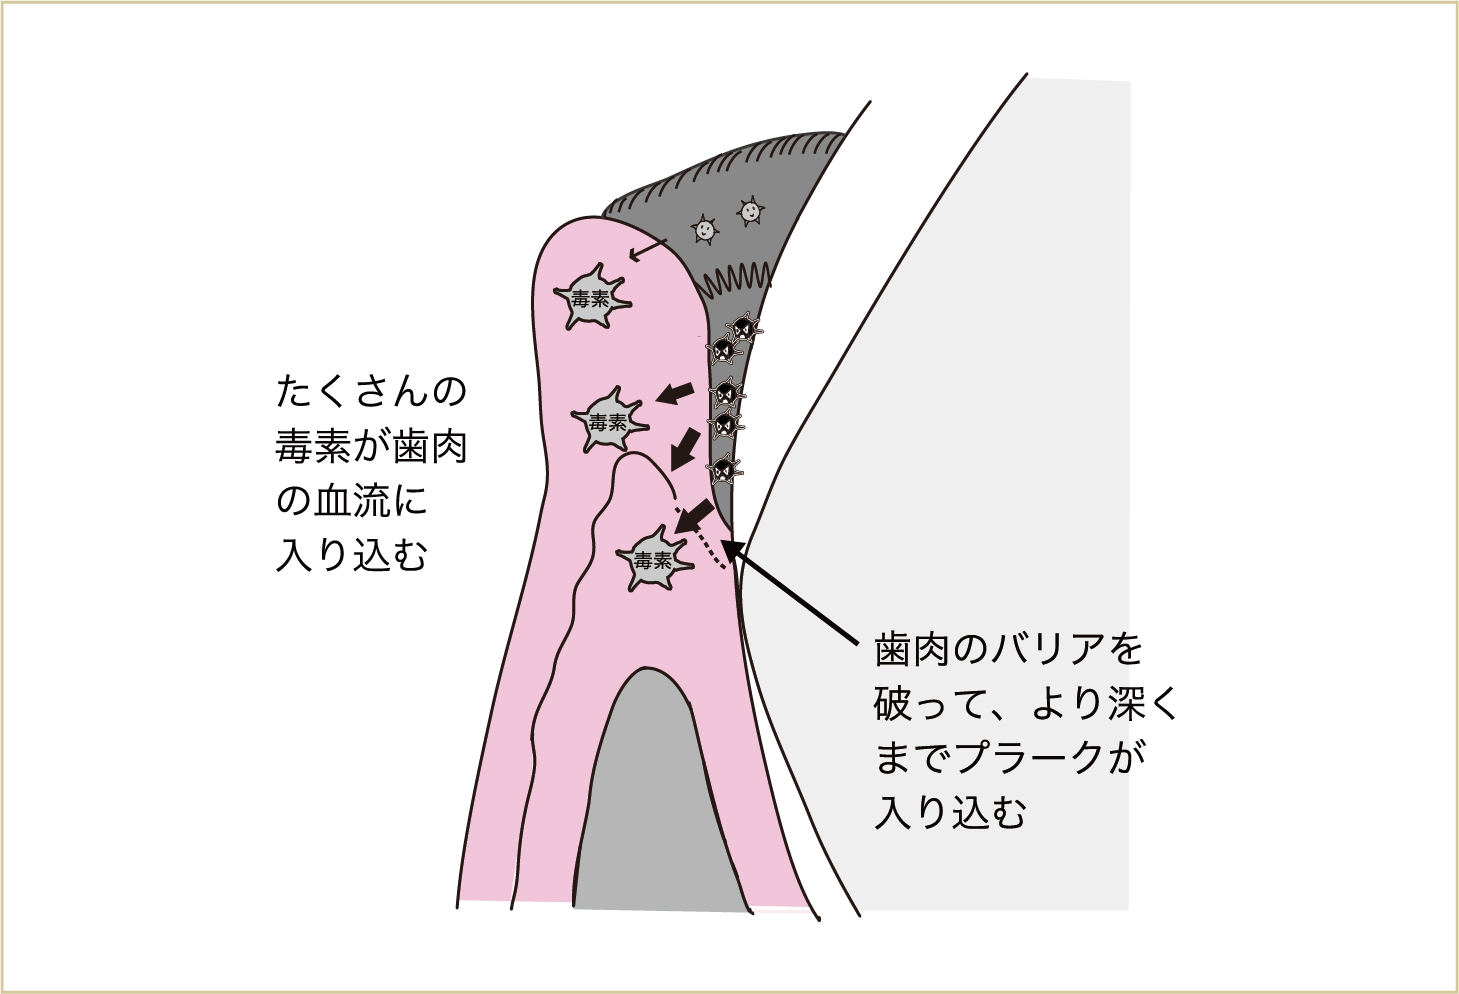

こうなると、歯肉が腫れる(新しいが弱々しい血管をたくさんつくって、新鮮な血流を増やす)だけでは対応できなくなってきて、今度は歯を支える骨が壊れはじめます。

つまり歯があるために、身体(血液中)に細菌が進入してくるのです。歯がなくなれば、これらの細菌がすみつく場所もなくなることを、身体はわかっています。歯のない部分の歯肉や頬には細菌はつくことができず、飲み込まれて胃液の酸で多くが死滅していきます。そこで、身体から歯を外してしまおうという反応が起こります。

この反応が歯周炎です。つまり、歯周病とは歯を支える骨が壊れることなのです。 歯を支える骨が壊れはじめると、プラークはこの壊れた部分、骨がなくなった部分にまで侵入してきます。これが繰り返されて、歯を支える骨が大きくなくなると、歯はグラグラと動揺してきます。

さらに病状が進行すると、細菌による毒素は、歯肉だけでなく、歯を支える骨や歯根表面にまで悪影響を与える。その結果として、歯を支える骨が壊れていく。